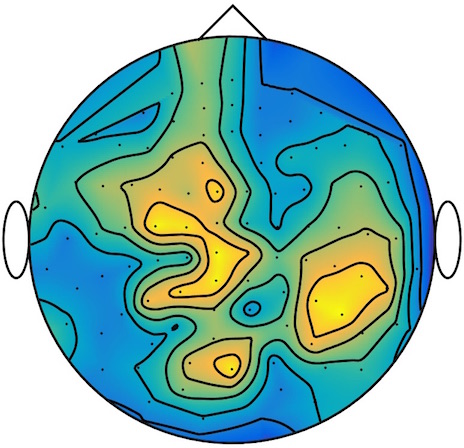

This results in two classes of recordings, one for each pressed button. We aim at computing a representative activity map for each class using Wasserstein barycenters. For each class we have recordings each having samples located on the vertices of an hexahedral mesh of a hemisphere (corresponding to a MEG recording helmet). These recorded values are positive by construction, and we rescale them linearly to impose . Figure 6, top row, shows some samples from this dataset, displayed using interpolated colors as well as iso-level curves. The black dots represent the position of the electrodes on the half-sphere of the helmet, flattened on a 2-D disk.

We computed TV-regularized barycenters independently for each class by solving (16) with the TV regularization using the projected gradient descent method (22). We used a squared Euclidean metric (24) on the flattened hemisphere. Since the data is defined on an irregular graph, instead of (23), we use a graph-based discrete gradient. We denote the graph which connects neighboring electrodes. The gradient operator on the graph is

The total variation on this graph is then obtained by using , the norm, i.e. we use in (23).

Figure 6 compares the naive barycenters (i.e. the usual mean), barycenters obtained without regularization (i.e. ) and barycenters computed with an increasing regularization strength . The input histograms being very noisy, the use of regularization is important to make the area of significant activity emerge from the noise. The use of a TV regularization helps to keep a sharp transition between active and non-active regions.